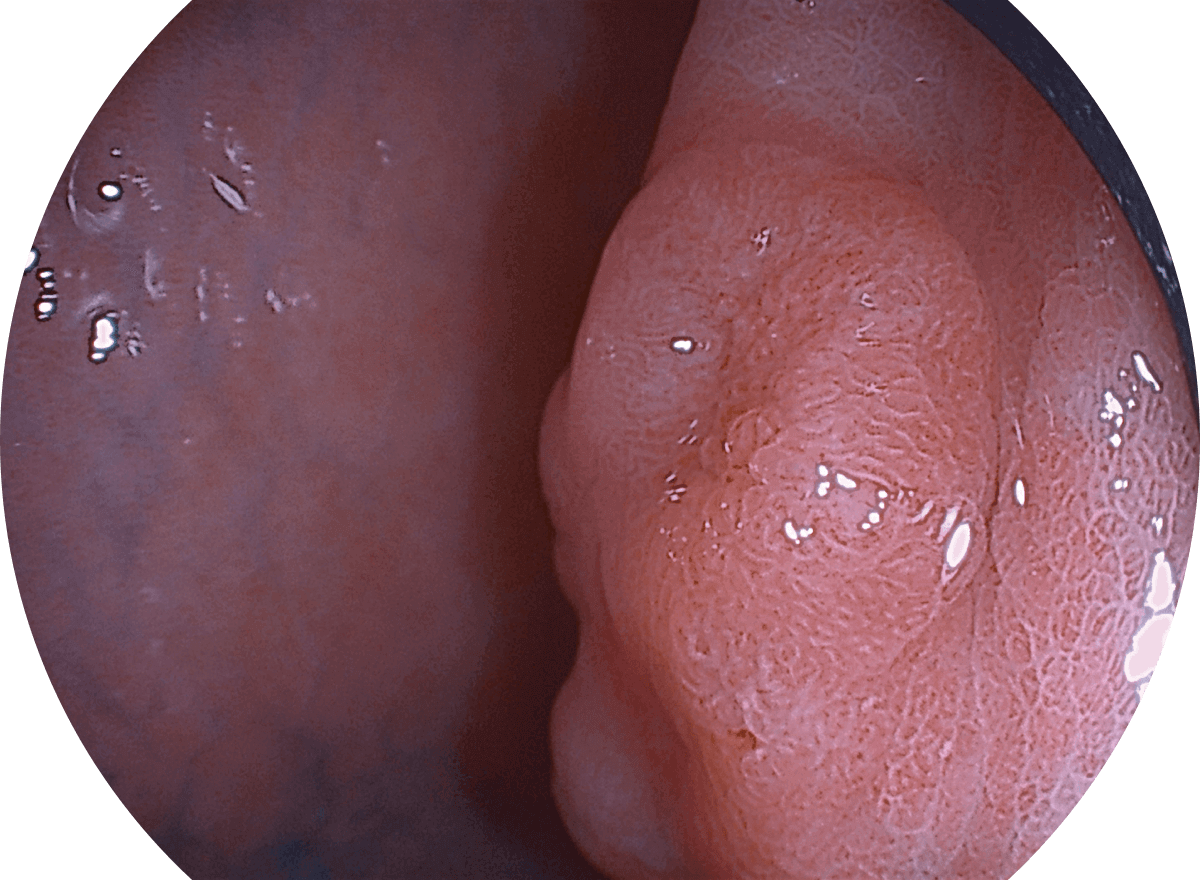

白光